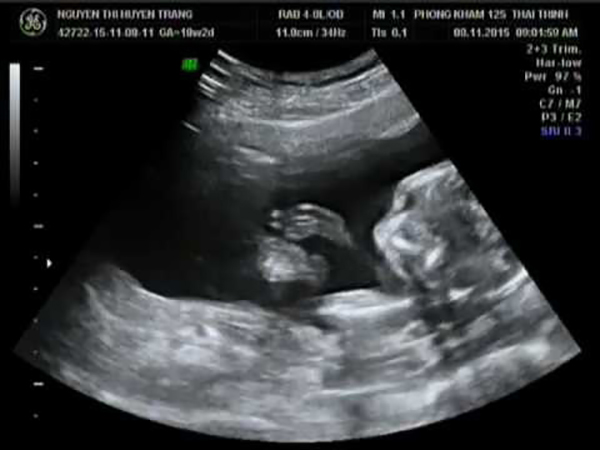

Siêu âm thai 2D có thể phát hiện nhịp tim của thai như thế nào?

Tim thai thường được phát hiện khá sớm ở tuần thứ 5 hay thứ 6 của thai kỳ. Khi siêu âm 2D thì các bác sĩ cũng dễ dàng phát hiện được nhịp tim của bé như thế nào. Đặc biệt vào thời điểm trước tuần 20 thì sẽ phát hiện ra rất nhiều các vấn đề tiềm ẩn khác nhau liên quan đến tim thai.

Ngoài siêu âm thai 2D thì các mẹ có thể theo dõi nhịp tim của thai qua thiết bị chọc dò thai nhi. Tuy nhiên, thiết bị này thường được dùng khi thai nhi đã khá lớn vượt qua 3 tháng đầu tiên của thai kỳ. Thêm vào đó, khi siêu âm thai 2D các mẹ còn có thể nhìn rõ thấy con của mình trong tử cung để biết được bé đang phát triển hết sức tốt đẹp.